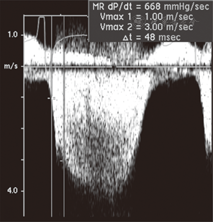

左心室dp/dt代表等容收缩期左心室压力上升的速率,在一定程度上反映的是左心室收缩功能,采用连续多普勒频谱测定获得,需要有二尖瓣反流(MR)的存在,A4C获得MR连续多普勒频谱,测定左心室压力上升速率。一般计算MR在1~3 m/s之间的时间差[3](dt),dp=4v12-4v32=36-4=32 mmHg(1 mmHg=0.133 kPa),因此,dp/dt=32/dt。dp/dt正常参考值>1 200 mmHg/s,dp/dt<1 000 mmHg/s为异常。见图4。

注:dp/dt等容收缩期左心室压力上升的速度